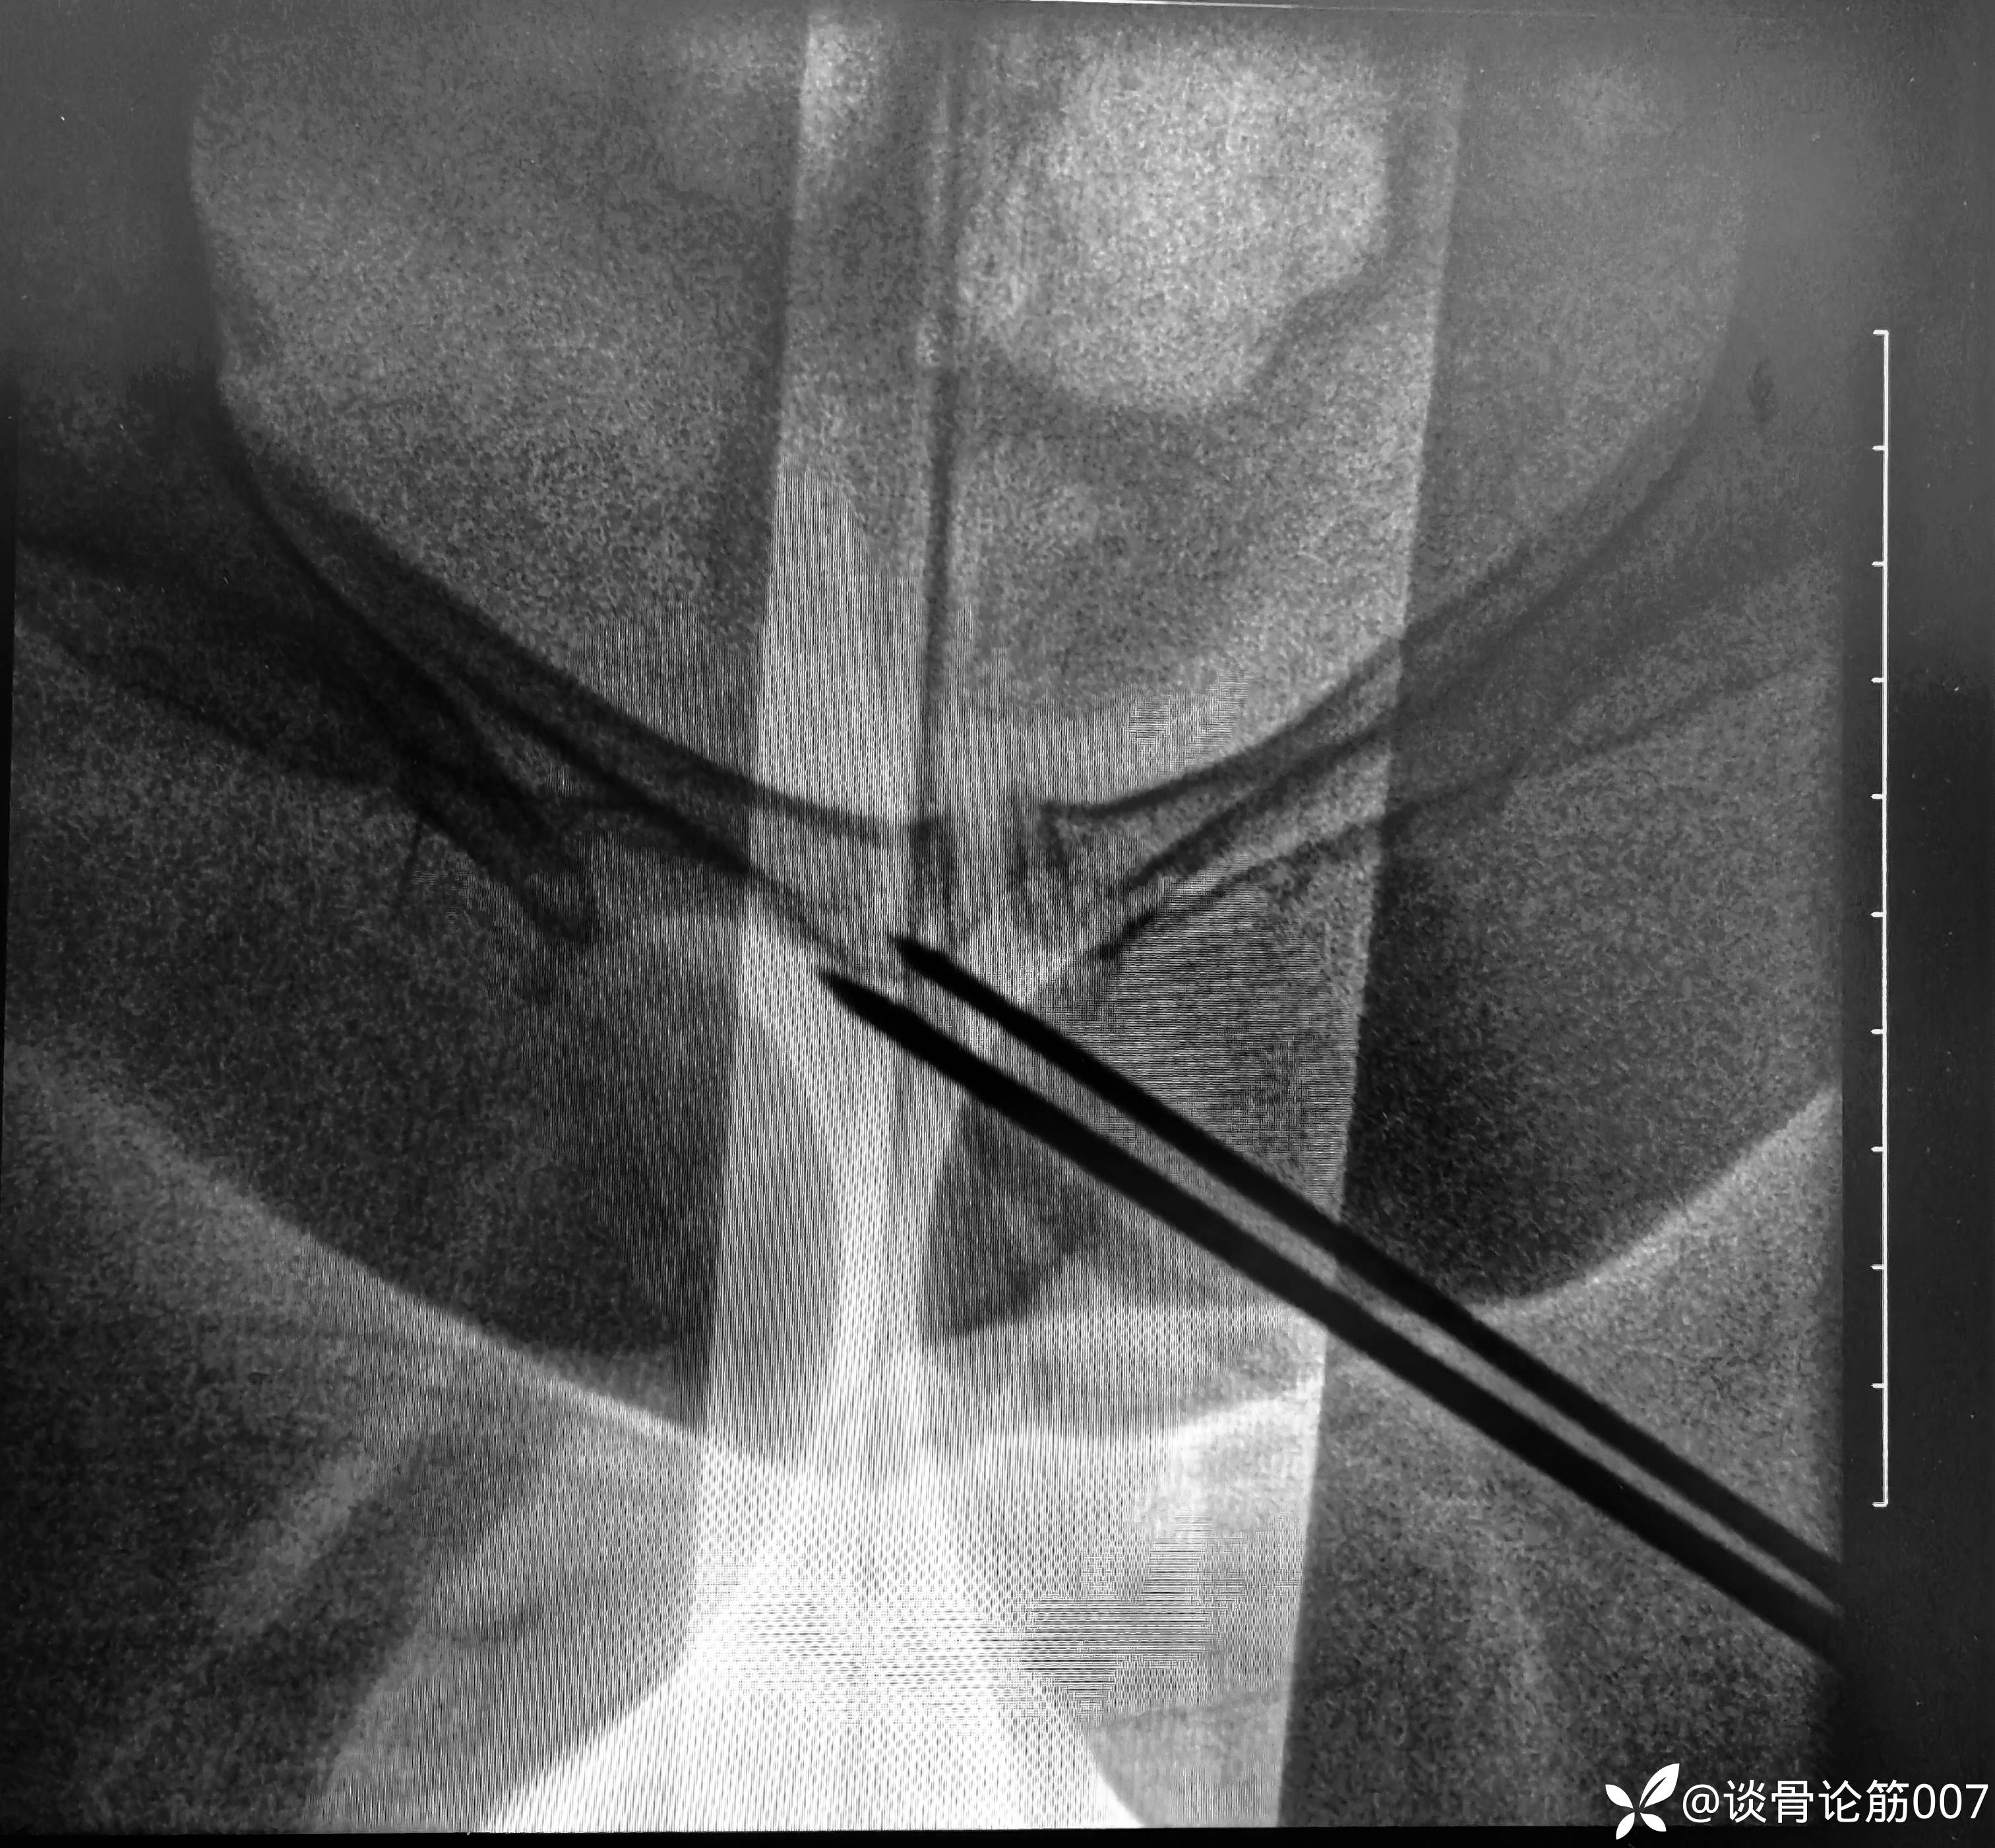

钉道方向还是有点差强人意

耻骨上支螺钉通道有限,如果有5.0空心螺钉更方便,但5.0螺钉没有长的,3.5长螺钉对耻骨上支骨折复位作用差一点,因为是实心,对操作要求更高一点。